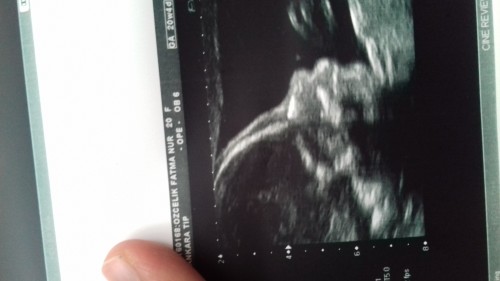

gebelikte ayrintili ultrason kacinci haftalarda yapilir ve onemi nedir gebelik hamilelik gebelikte beslenme gebelik hesaplama gebelikte kilo alimi hamilelik ve gebelik hakkinda